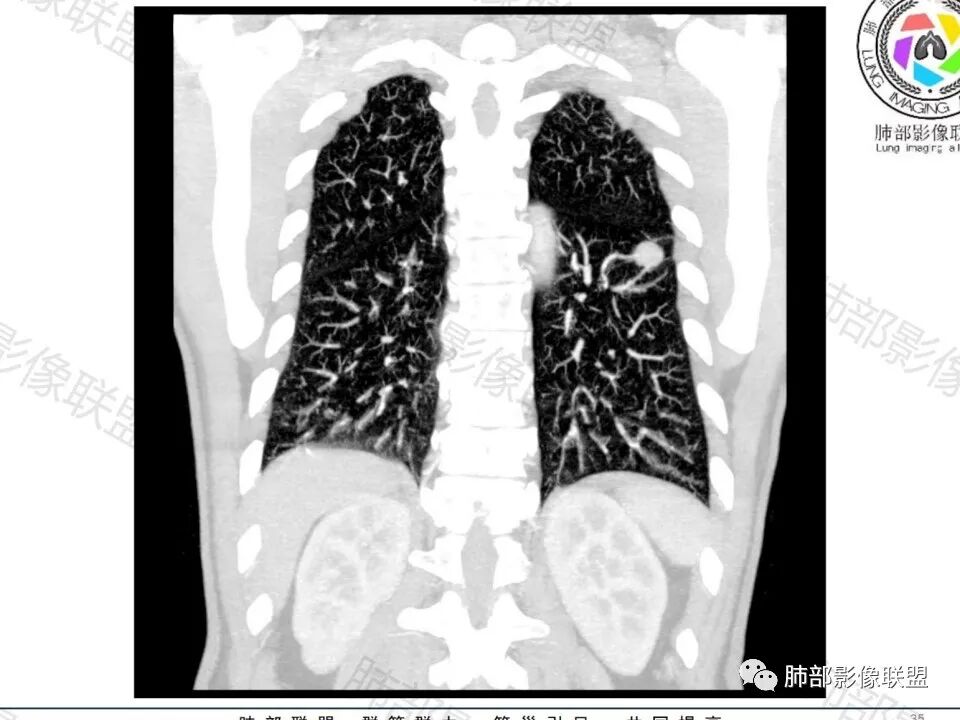

老年男性,无症状,肺气肿背景

类圆形,边缘稍平直,周围晕中细微毛刺,密度均匀,均匀强化,血管走形自然,稍牵拉扭曲,支气管在近端堵塞

多发类似结节

1、炎性结节,多发,类似,晕,隐球菌?

2、恶性:多发:转移瘤?肺癌并多发转移瘤?